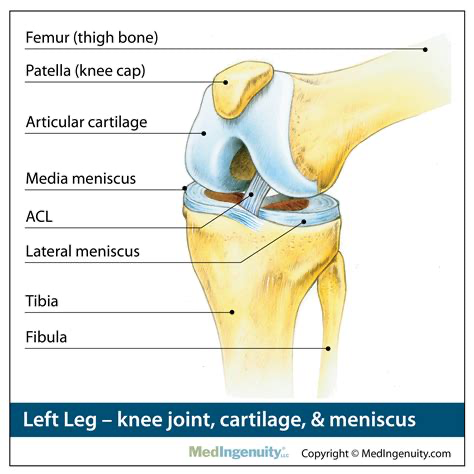

4. JOINT SIZE (ANKLES, WRISTS,KNEES, AND ELBOWS)

- In the case of joints, it is absolutely better to have smaller joints since they make the nearby muscle look big in comparison. This is because the taper from the muscle belly to joint is sharper.

- Consequently, it enhances the biceps, forearms, calves and thighs. The body looks more sculpted

- On the other hand, with bigger joints, it is simply much harder to create the illusion of mass. The muscles look less flat and dont "pop" the same way.

- Even with great size it is perhaps not really possible to make up for the visual decline noticed from having bigger joints. The cartoonish arm that is popular with the Classical physique is then out of reach.